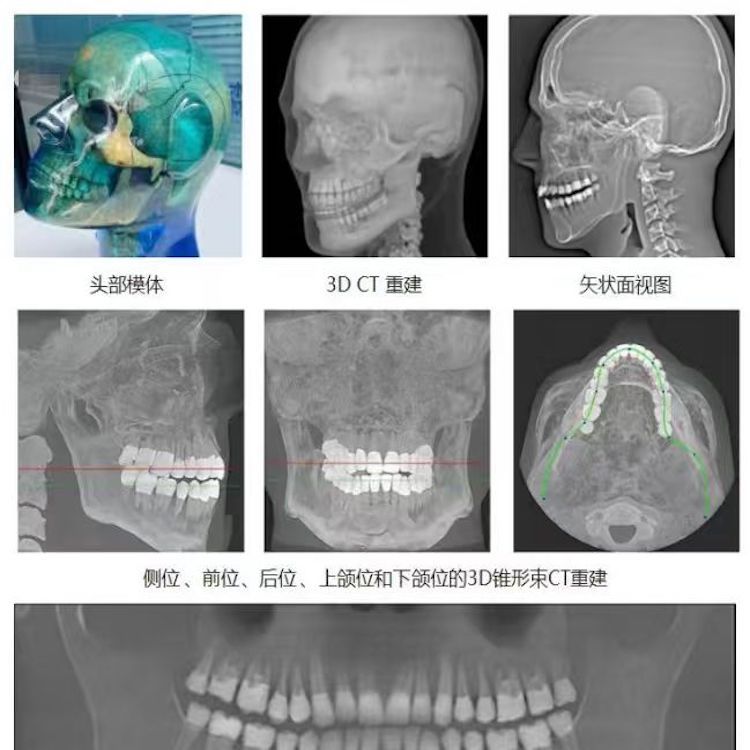

頭部模體

頭部模體是頭部診斷放射學的參考標準,該模體旨在協助技術和臨床人員,在大多數需要精細解剖細節的放射學程序中選擇、監測、培訓和驗證掃描參數。 模體為研究人員、臨床醫生和技術人員提供了一致性的工具。它非常適合確定最佳系統設置、調試新設備、監測系統性能和培訓牙科X射線、全景X射線、CT和錐束CT程序。 這個模體包括一個可調節的支架,用于在錐束 CT 或全景X射線系統中定位。模體的下頜略微張開,前牙垂直排列,以復制正確的咬合引導定位 。 請注意,實際咬合引導無法在這個產品中定位。 頭部模體是由專有組織等效材料制成的。由組織模擬樹脂制成,這些樹脂模擬X射線對人體的衰減特性,適用于CT和治療能量范圍(50keV-25MeV)。 模體在大小和結構上都近似于平均男性頭部 。該模體包括詳細的3D擬人化解剖結構, 包括大腦、骨骼、喉、氣管、鼻竇、鼻腔和牙齒。骨骼包括皮質和骨小梁的分離。牙齒包括明顯的牙本質、牙釉質和包括神經的牙根結構。鼻竇完全張開。

頭部模體特點 1. 詳細的解剖特征; 2. 確定法蘭克福平面以確保正確對齊; 3. 50 keV 至 25 Mev 的組織等效值; 4. 具有六個自由度的定位支架; 5. 包括泡沫內襯手提箱; 6. 12個月保修。

功能和應用 1. X射線 ,全景X射線 ,CT和錐束CT系統; 2. 學習如何正確定位頭部以獲得最佳圖像; 3. 測試重建技術和算法 ,用于植入物規劃和頜面部重建; 4. 在實施新設備和新技術期間培訓并評估人員; 5. 驗證圖像質量的一致性。